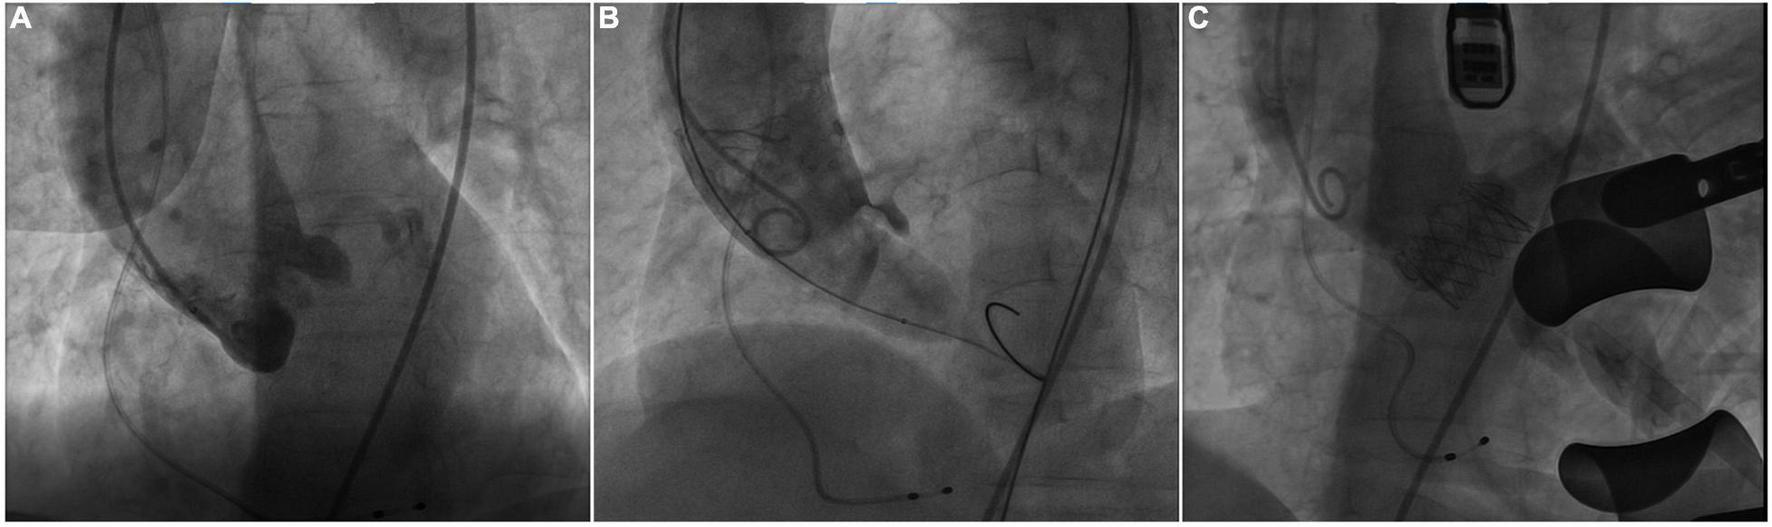

The procedure was performed in our hybrid operating room for TAVR as previously described (4). At the beginning of the TAVR procedure, bilateral coronary arteries were patent under intraoperative fluoroscopy (Figure 2A). Balloon pre-dilatation was routinely performed to assess the supra-annular structure and evaluate the risk of coronary occlusion using a 23 mm × 40 mm Z-Med™ balloon based on the annulus perimeter derived diameter (6). Unexpectedly, the right coronary artery was invisible and the blood flow reduced in the LMA, immediately after balloon dilatation (Figure 2B), indicating RCA completely occluded and LMA partially occluded by the native left coronary leaflet. The patient’s blood-oxygen saturation dropped sharply from 100 to 72%. Intraoperative transthoracic echocardiography revealed a transvalvular gradient of 20 mmHg following balloon deflation. Therefore, the multidisciplinary team decided to suspend the procedure. A careful and comprehensive reassessment of the patient’s anatomy was performed and the transapical TAVR with J-valve (JieCheng Medical Technology Co., Ltd., Suzhou, China) was planned for safety consideration.

FIGURE 2

Intraoperative fluoroscopy. (A) Fluoroscopy showed bilateral patent coronary arteries before balloon pre-dilatation. (B) The right coronary artery was invisible and reduced blood flow in the left coronary artery during the balloon dilatation. (C) Fluoroscopy showed the patency of bilateral coronary arteries after J-valve deployment.

Subsequently, transapical TAVR with J-valve was performed under general anesthesia 3 days later. A 23-mm J-Valve system was introduced and repeatedly adjusted to ensure the three graspers were properly placed in the left-, right-, and non-coronary sinuses and accurately surround the native leaflets. The prosthetic valve was gradually released after positioning at 1 cm below the aortic annulus under rapid ventricular pacing. The procedure was uneventful and the final fluoroscopy showed the proper position of the prosthetic valve and the patency of bilateral coronary arteries (Figure 2C). The final echocardiography showed mild perivalvular leakage and the residual transvalvular gradient was 3 mmHg. The patient was discharged without obvious symptoms of heart failure and could carry out daily activities with ease after discharge. At 30 days follow-up, she had an NYHA class II functional status and echocardiography showed normal aortic valve function with a transvalvular mean gradient of 5 mmHg.